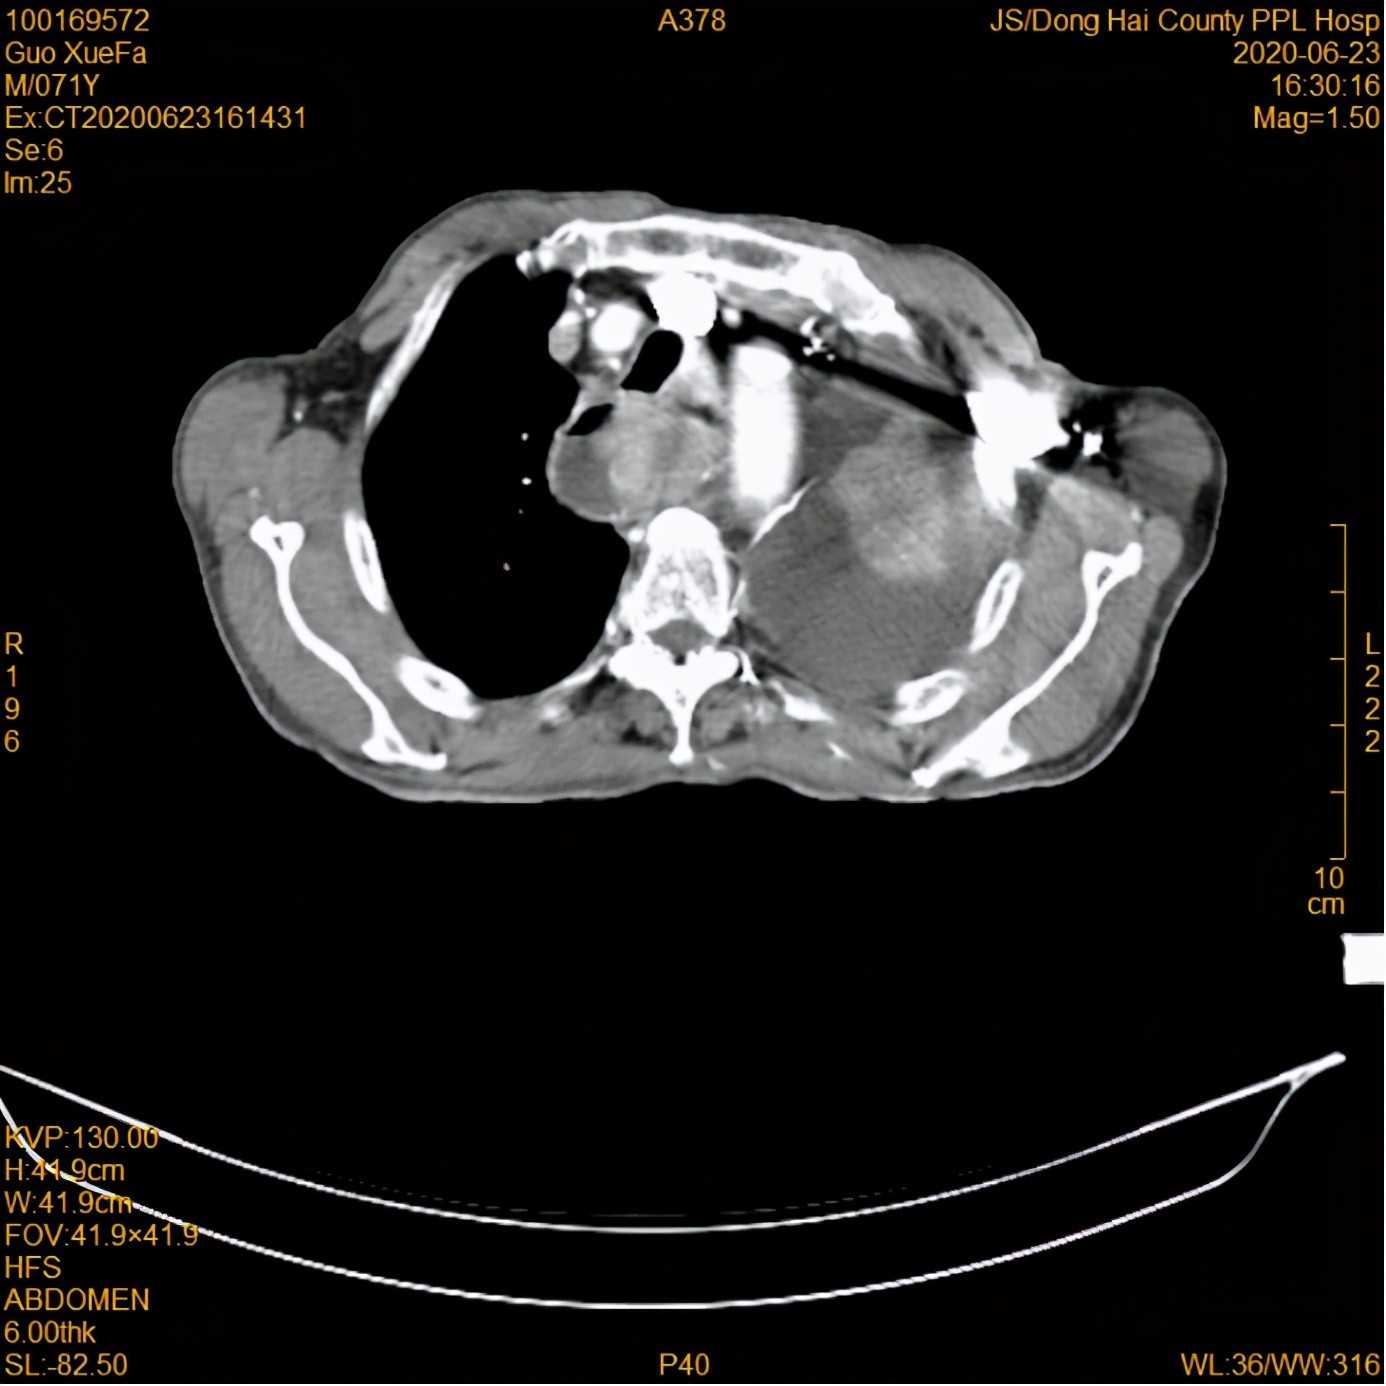

放疗前

16日,郭大爷的女儿带着郭大爷来到我院就诊,经全面检查,郭大爷被确诊为食管癌(伴纵隔、肺门、腹膜后淋巴结转移; 胸腔积液)。